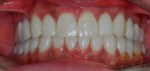

When passion becomes your profession..making people smile becomes your habit! here’s my recent case of cosmetic dentistry: